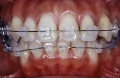

治療後5年経過時